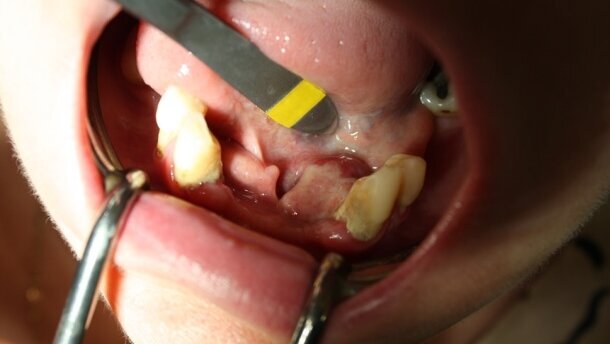

52-letni pacjent, ogólnie zdrowy, skierowany do poradni chirurgii stomatologicznej z poradni ogólnostomatologicznej. Podawał pojawienie się i powiększanie przez ok. 8 miesięcy zmiany okolicy zęba 34. Potwierdzono obecność zmiany o kształcie elipsoidalnym, wnikającej szypułą do kieszonki zęba 34 i położoną dystalnie (Ryc. 6). Pobrano w znieczuleniu miejscowym 4% artykainą z dodatkiem noradrenainy wycinek próbny, utrwalony 10% formaliną. Otrzymano wynik: epulis gigantocelullaris. Także tutaj nie stwierdzono w rtg cech lizy tkanki kostnej.

W znieczuleniu miejscowym 4% artykainą z dodatkiem noradrenaliny usunięto operacyjne guz wraz z zębem 34. Ponadto, uwidoczniono niewielkie „poszarpane” fragmenty blaszki przedsionkowej i okolicy dystalnej zębodołu 34. Wykonano dodatkowo obwodową ostektomię w otoczeniu guza z wykorzystaniem narzędzi maszynowych, analogicznie jak w opisanym wcześniej przypadku. Ranę pokryto zmobilizowanym i przesuniętym dystalnie płatem bez napięcia i zaopatrzono szwami z polidioksanonu w rozmiarze 4-0 oraz w okolicy zęba 33 nylonem 6-0 (Ryc. 7-9). Badanie histopatologiczne całego guza potwierdziło rozpoznanie z wycinka próbnego (Ryc. 10-11).